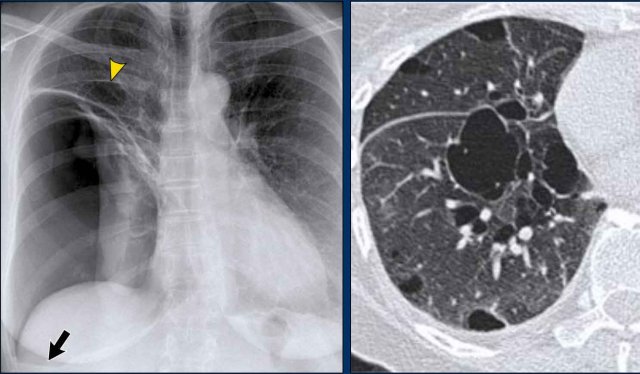

Displacement of the Azygoesophageal Line (2) – Subcarinal Lymphadenopathy

A common cause of displacement of the azygoesophageal line is subcarinal lymphadenopathy (station 7).

On the chest X-ray, note superior displacement of the azygoesophageal line just below the carina, consistent with enlarged subcarinal lymph nodes (black arrow).

Additional right paratracheal lymphadenopathy is seen, displacing the right paratracheal stripe (white arrow) and deviating the trachea to the left.

Continue with PET-CT...

PET Imaging

• PET-CT demonstrates extensive hypermetabolic lymphadenopathy in the mediastinum and neck, which is more conspicuous than on chest radiography.

• Cervical lymph nodes are involved—an important finding as they are accessible for biopsy.

Continue with images of CT and ultrasound...

CT Imaging

• Contrast-enhanced CT shows bulky subcarinal lymphadenopathy displacing the azygoesophageal recess and compressing the left atrium.

• Biopsy of a cervical node confirmed small cell lung carcinoma.